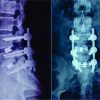

Although the patient experienced back pain, no neurological impairment was noted. Fluoroscopy and X-ray examinations were inconclusive in locating the remaining catheter fragment, and a computed tomography (CT) scan provided no helpful information (Fig. 2 and 3).